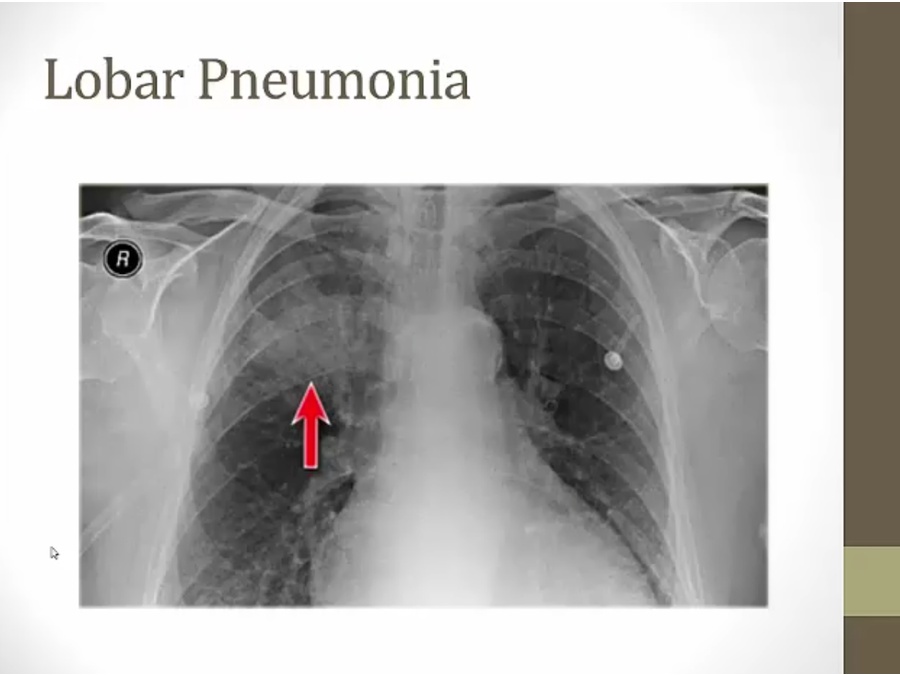

black arrow: lung

RUL infiltrate